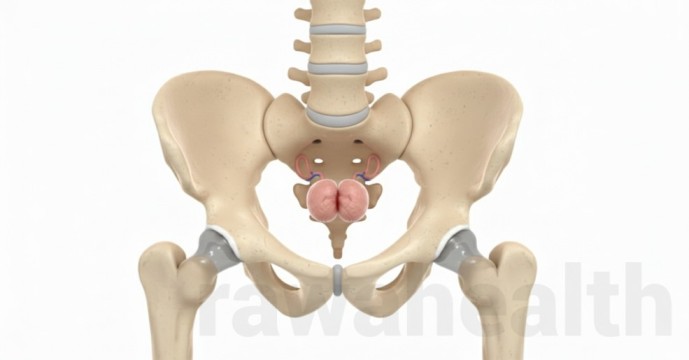

Hymenoplasty Surgery Hymenoplasty surgery is a minor gynecological procedure that repairs or reconstructs the hymen, a thin membrane located at the vaginal opening. Women choose this surgery for personal, emotional, or medical reasons. Advances in modern gynecological techniques have made hymen repair a safe, quick, and confidential procedure with minimal downtime. This detailed guide explains […]